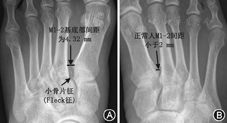

Lisfranc关节损伤患者的初诊X线漏总诊率为14.9%(18/121),其中99例Myerson型损伤漏诊率为7.1%(7/99),而漏诊的7例患者均发生在Myerson Ⅱ型患者中;另外22例Nunley-Vertullo型损伤中漏诊率为50%(11/22),两者比较差异有统计学意义(P=0.016)。骨折脱位者正位上表现为M2基底部榫眼样凹槽结构消失,M2基底部变浅,M1~M5的一根或多根向内侧或外侧移位(图2),Ⅰ型13.1%(13/99),Ⅱ型82.8%(82/99),Ⅲ型占4.1%(4/99)。99例患者中M2外移位占75.8%(75/99),关节间隙>2 mm者(图3)占67.7%(67/99),平均为2.0~18.5(4.6±2.5)mm,其余患者间距<2 mm。99例患者中第1跖骨基底部与第2跖骨基底部间存在小骨片/小斑片征(Fleck)者(图3)为47.5%(47/99),行足侧位负重或非负重X线可显示M1~M5中的一根或多根相对于楔骨的背或跖侧移位,99例患者中44.4%(44/99)存在背侧移位,6.1%(6/99)为跖侧移位,跖骨侧脱位可导致X线图像上Myerson分型的不典型,50例移位者中累及M2基底部者占90%(45/50)。22例Nunley-Vertullo型损伤患者中Nunley-Vertullo Ⅰ型为5例,Ⅱ型为16例,Ⅲ型为1例,17例患者M1~M2间隙增大2 mm,平均为2.3~6.2(4.0±1.1)mm,间隙间存在小骨片患者占45.5%(10/22),只有1例患者即Ⅲ型者存在M2背侧移位,余未见背侧或跖侧移位。本组中<18岁患者,6例患者行X线检查,但仅2例可观察到骨折线穿过骺线同时累及骨骺与干骺端,2例患者M1~M2间距>2 mm,2例患者Fleck征阳性。

Lisfranc关节为中足与前足的重要分界和连接。从功能和解剖结构来看,Lisfranc关节关节面连线为"S型",被分为"三柱",内柱为C1-M1相关节,中柱为C2-C3-M2-M3相关节,外住为Cu-M4-M5相关节,M1-M5基底部横弓似"罗马拱桥",此弓主要靠M2基底部维持,故此M2又称为"基石"(key stone),X线足正位成像上,M2插入M1、C1-3、M3构成的"榫眼"样凹槽中,此结构称为榫眼关节(mortise joint),M2与M1基底部高度相距1 cm,M2与M3基底部高度相距0.5 cm[5,6],而M1~M2基底部水平距离应<2 mm(图1),凹槽的深度对关节稳定性亦起到重要作用,Mortise关节凹槽的变浅是Lisfranc关节损伤的危险因素之一[7]。

Lisfranc关节损伤X线存在一定的漏诊率,对于临床上怀疑Lisfranc关节损伤,而X线表现阴性时,需行CT或MR检查,CT可较佳探测骨质损伤情况,MR可较佳显示Lisfranc韧带损伤。X线上M1~M2>2 mm、M1~M2间存在小骨片时,为Lisfranc关节损伤的可靠征象。